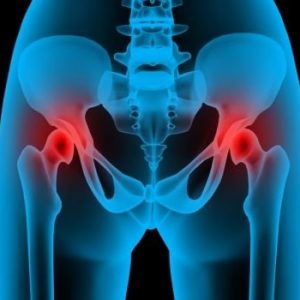

При жените тазовите стави трябва да бъдат гъвкави за носене на деца и т.н. лигаментите омекват и се разтягат по-лесно. Понякога те не се стягат след раждането и следователно позволяват твърде много движение: оттук „сакроилиачна нестабилност“.